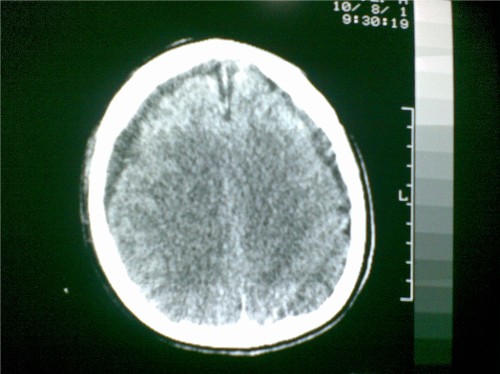

标题: CT28096:男,75岁,外伤10天后,现在恶心、呕吐。是硬膜下积 [打印本页]

标题: CT28096:男,75岁,外伤10天后,现在恶心、呕吐。是硬膜下积

硬膜下积液、右侧基底节、左侧放射冠腔梗。

硬膜下积液、多发性腔梗。

1)双侧额颞顶部硬膜下积液;建议必要时复查。2)多发性腔隙性脑梗塞。